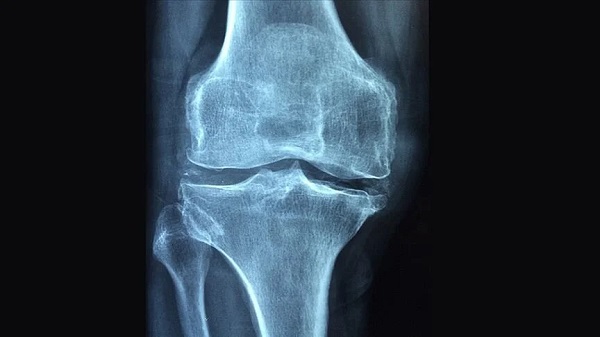

Kalsiyum seviyelerinin dengelenmesinin, kemik sağlığı ve diğer sağlık sorunlarının önlenmesini sağladığına dikkat çeken Dr. Öğr. Üyesi Erdem, kalsiyumun vücudumuz için önemini şu şekilde açıkladı: “Kalsiyum, kemik ve dişlerin sağlıklı kalması için önemlidir. Kemiklerimiz, vücudumuzda depolanan kalsiyumun yaklaşık yüzde 99'unu içerir. Kalsiyum, ayrıca kasların kasılması, kalp ritminin düzenlenmesi ve sinir sistemimizin düzgün çalışması için de gereklidir. Vücudumuz, bu işlevler için yeterli miktarda kalsiyum sağlayamadığında, sağlık sorunları ortaya çıkabilir."

Hem kalsiyum eksikliği hem de yüksekliğinin ciddi sağlık sorunlarına neden olabileceğini, ancak kalsiyum eksikliğinin toplumda daha yaygın olduğunun altını çizen Dr. Öğr. Üyesi Erdem, “Kalsiyum eksikliği kemik sağlığı sorunlarına, osteoporoz ve daha sık kemik kırılmalarına neden olabilir. Kalsiyum yüksekliği ise böbrek taşı ve böbrek yetmezliği gibi komplikasyonlara neden olabilir” diye konuştu.